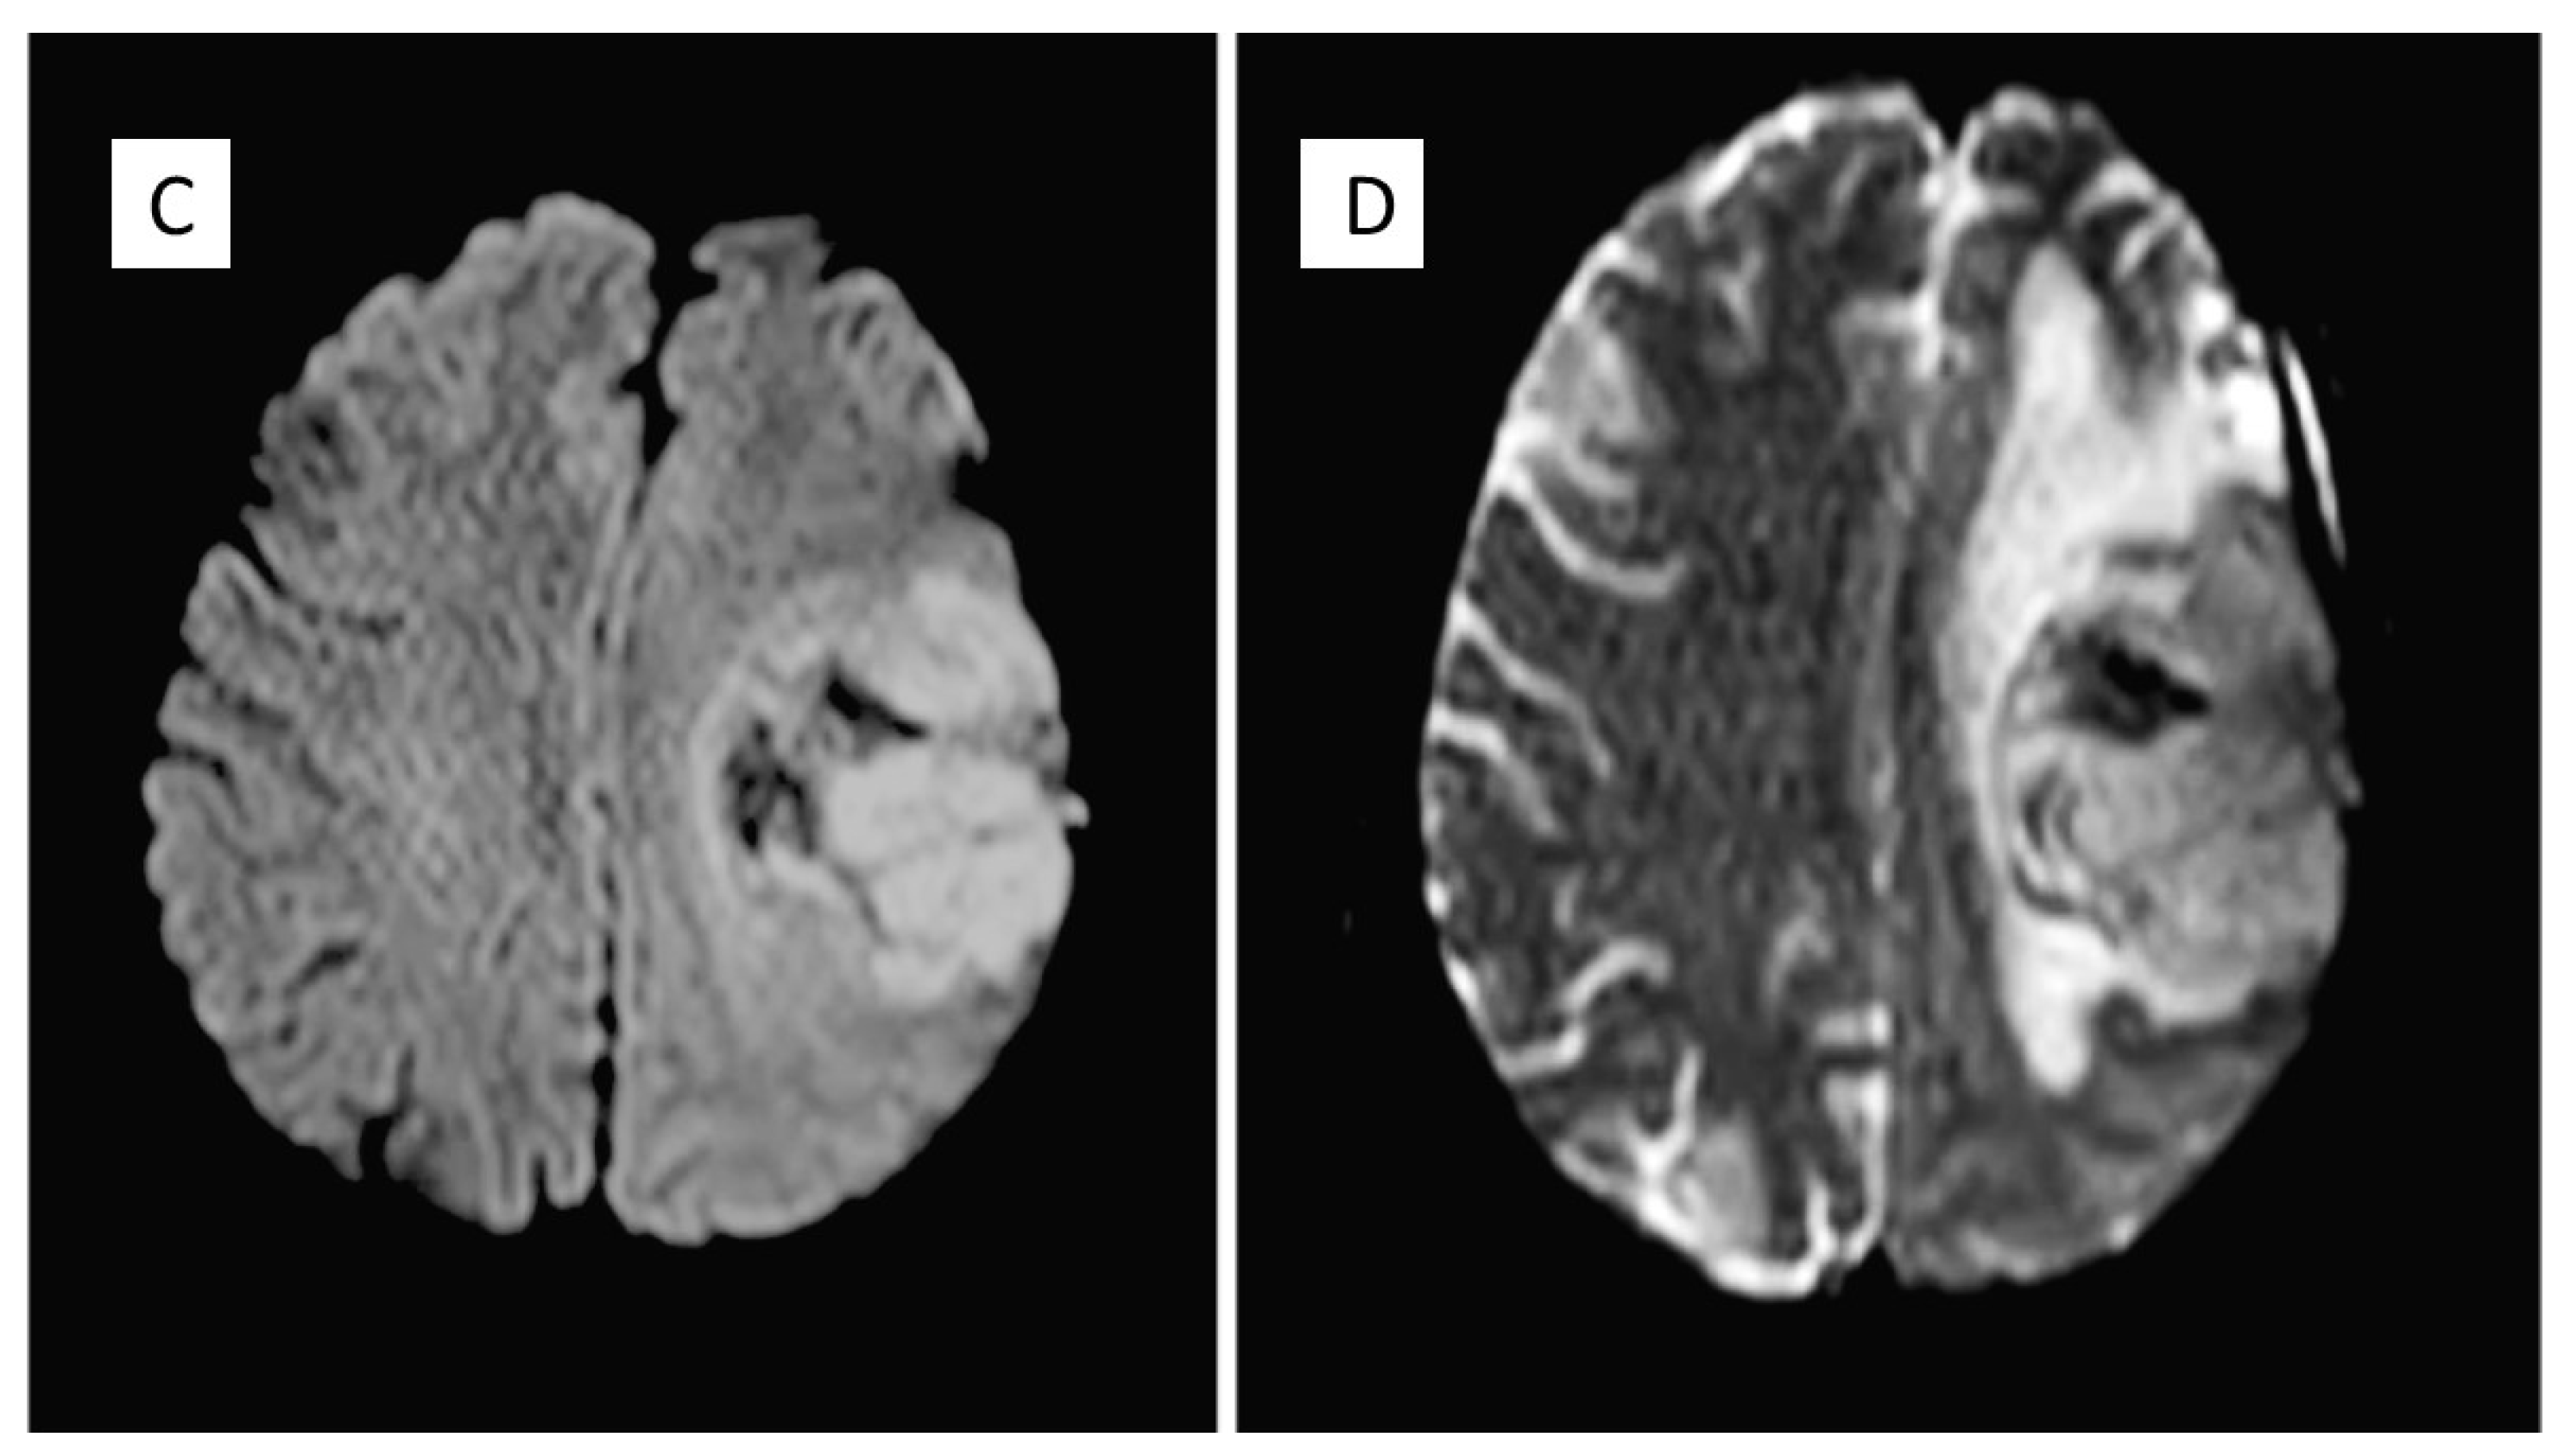

| 2010 | Headache, speech difficulties and hypersomnia | Neoplastic lesion in the left frontparietal area compatible with papillary meningioma | Surgical removal and radiotherapy adjuvant treatment |